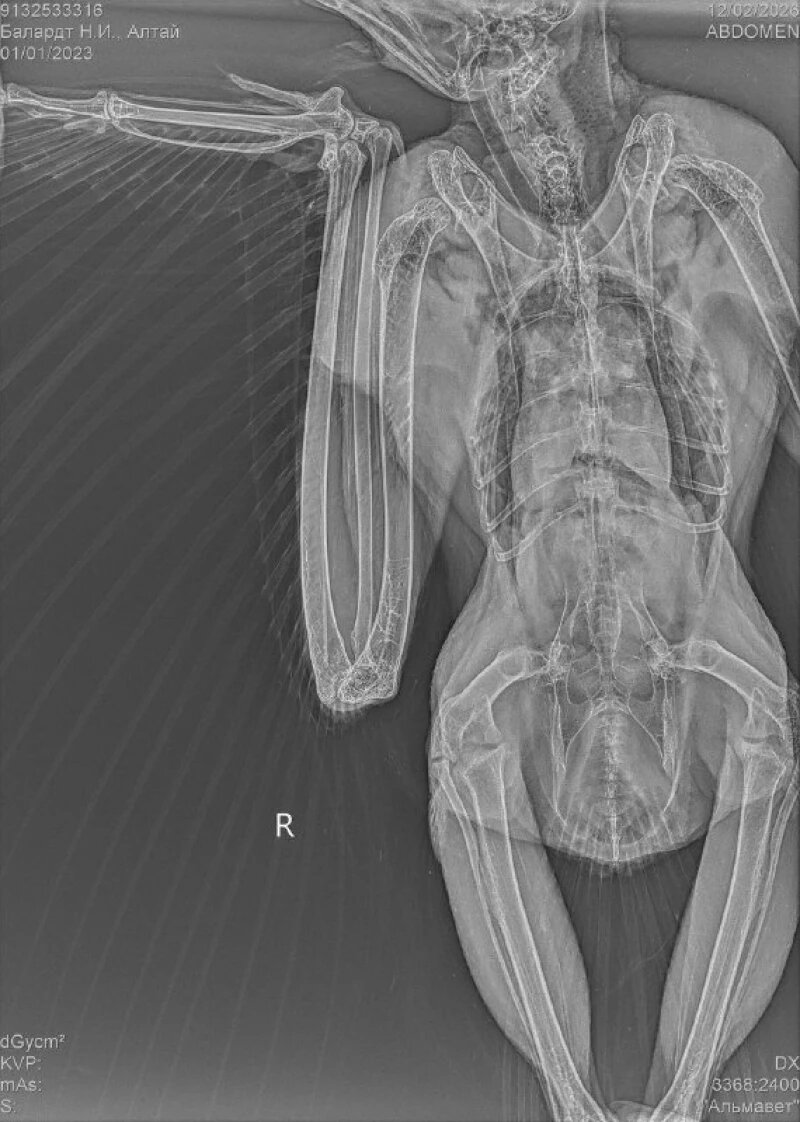

Пернатого странника передали в клинику «Ноев Ковчег» в Барнауле. Ему дали имя Алтай. Из-за контузии он не видит и не слышит. Рентген показал множественные ушибы и травмы, которые появились после удара автомобиля.

Есть риск потери зрения, но врачи делают все возможное, чтобы этого избежать. Правый глаз восстановить не удастся, но есть надежда спасти левый.